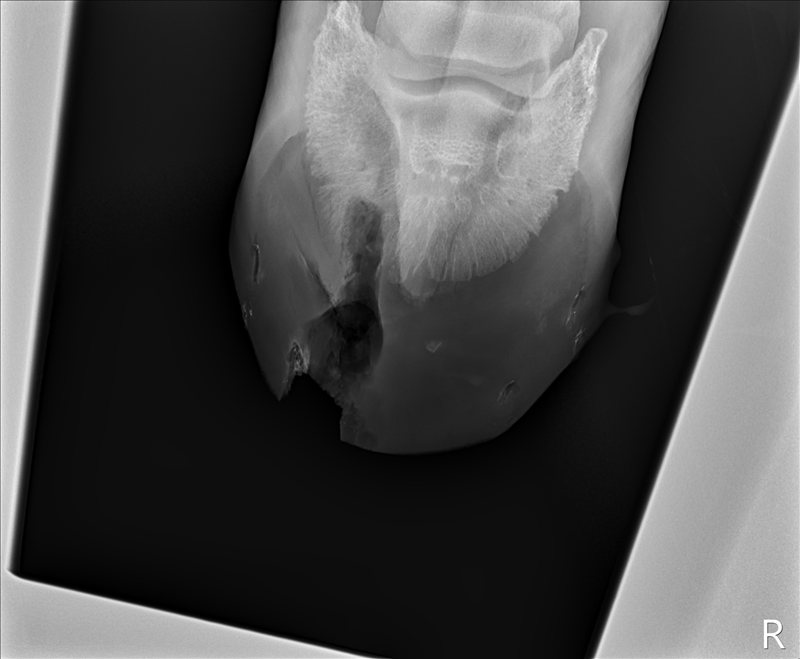

The surgeon came to find us and show us the x-rays in a few more minutes. He said he evaluates surgery on two points: his gut feeling and the clinical signs. In this case, he said, both were good. He said he would be surprised if Tris didn’t return to 100%. Hooray!

![]() |

| X-ray taken during surgery with a probe inserted to confirm that they were headed in the right direction. |

| Side view of same. |